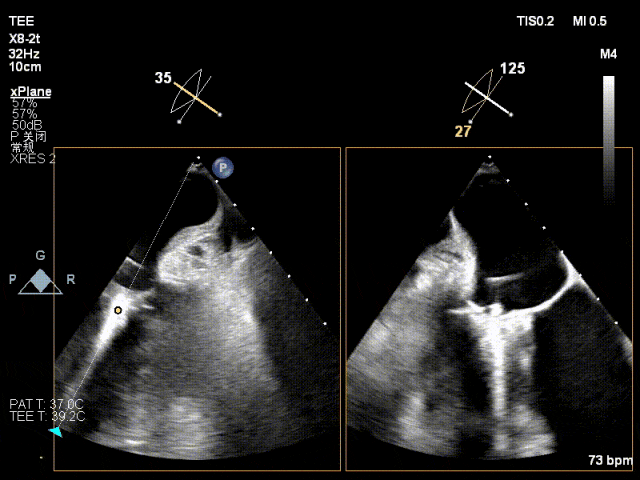

术前二尖瓣重度反流,后叶栓系瓣叶对合不良

一枚MitraClip XTW夹持后,反流降至轻度

肺静脉逆流改善